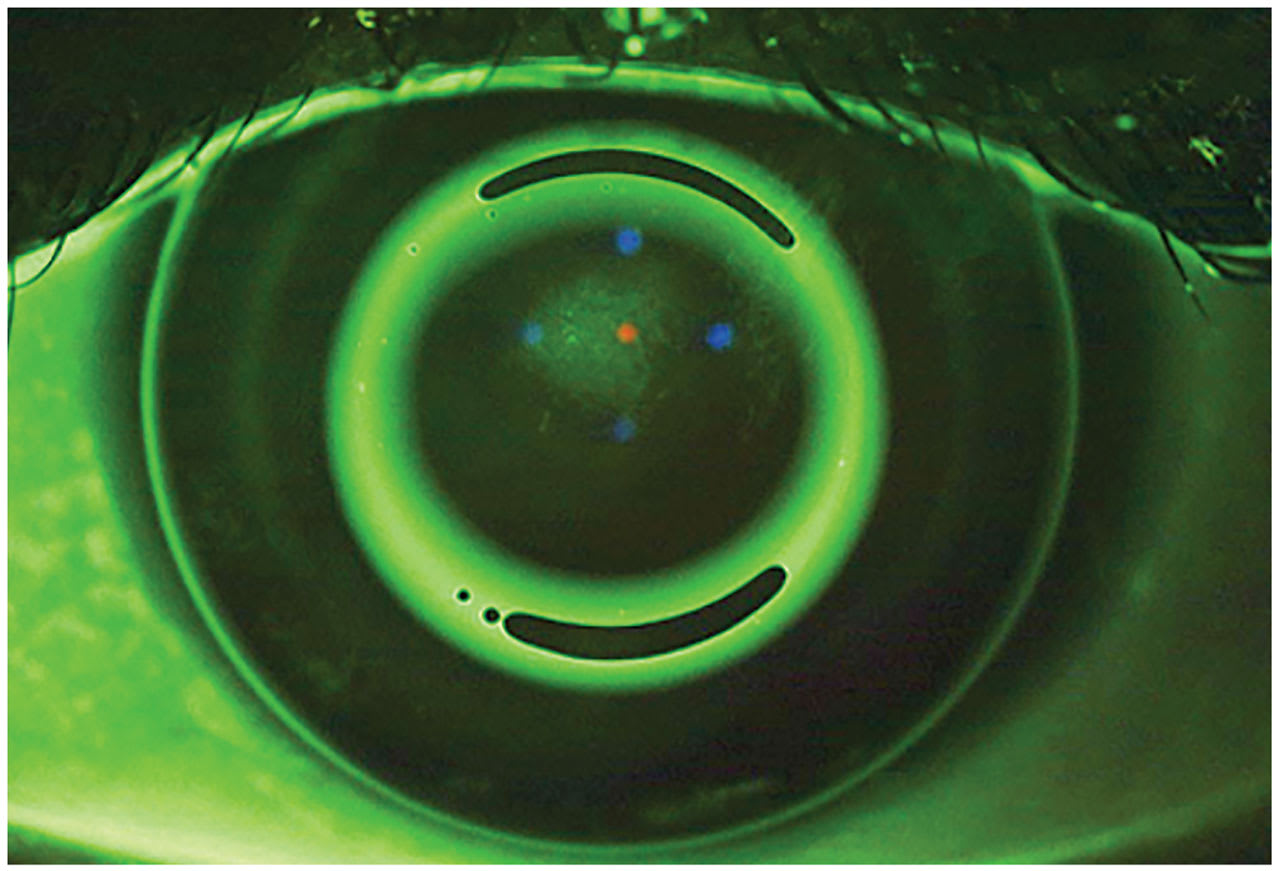

Start by shifting focus away from the center bull’s-eye to the dark areas of the sodium fluorescein (NaFl) pattern. The outermost dark ring is the alignment zone, and designing a lens that is well-aligned with the peripheral cornea creates an effective ortho-k lens. Think of the alignment zone like the landing curves of a scleral lens. Sometimes you can get away with a spherical landing, but you often need toric or even quadrant-specific curves to achieve the desired fit.

Figure 1A shows an even alignment zone 360° around the center bull’s-eye, whereas Figure 1B shows NaFl bleeding into the inferior quadrant of the alignment zone. The lack of a defined bull’s-eye due to a poor fitting alignment curve can negatively impact the forces that encourage epithelial cell migration. This can lead to decreased acuity or residual refractive error. Similar to scleral lens fitting, adding toric or quadrant-custom peripheral curves can improve the outcome of this process.